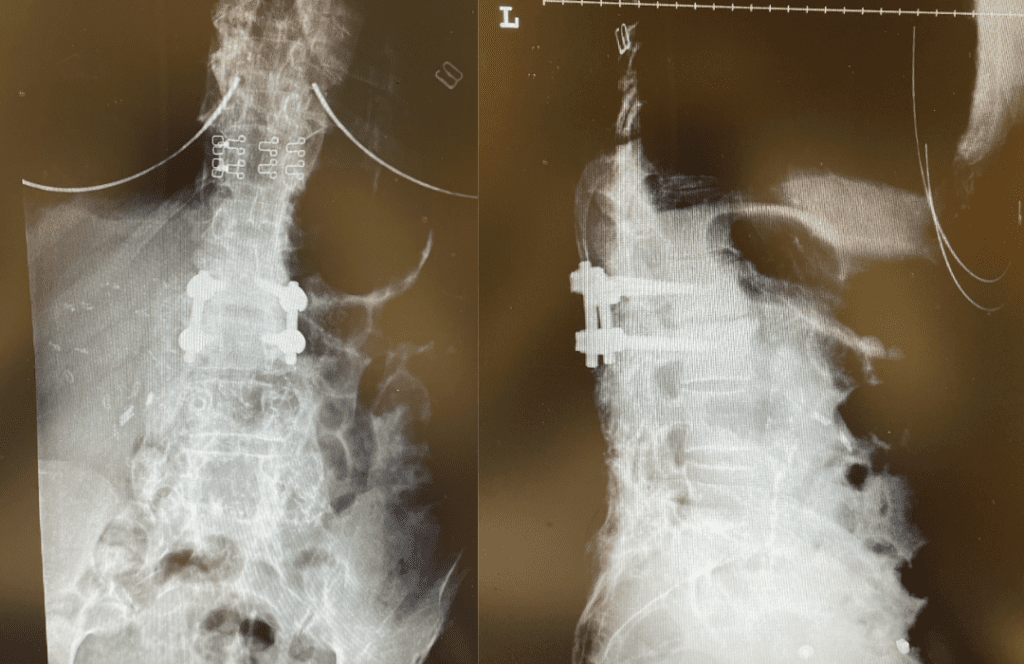

During the decompression we removed the inferior facets of L2 after the L3 screws were removed. This is a key maneuver in a revision decompression as it allows access to a dissection plane that allows the foramina and both L3 nerve roots to safely be decompressed. The L2 lamina is removed as well as a dissection plane at the inferior aspect of the bone is developed with an up biting curette. Because of her solid fusion it was only necessary to add new screws at L2 and L3 giving her a shorter construct and less potential stress at the next segment. Post operatively the patient did very well with resolution of leg pain and improved strength in her proximal leg (Figure 3).

Figure 3. Post Op AP and lateral x-rays after L2-3 instrumented fusion